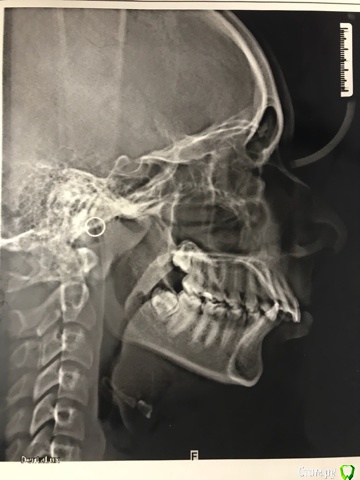

В 15 лет поехали на консультацию в ФГУ ЦНИИСиЧЛХ, диагноз: сочетанная скелетная деформация челюстей, верхняя прогнатия, нижняя ретромикрогнатия, дистальная оклюзия, глубокая резцовая дизокклюзия, сагитальная щель 10 мм, сужение деформация зубоальвеолярных дуг, скученное положение зубов, протрузия резцов, аномалия положения зачатков 8 моляров, уздечки нижней губы, мелкое предверие рта, индивидуальная макродентия.

В Москве на консультации вопрос ортодонтического лечения конкретно не обсуждался, но было рекомендовано 4зуба не удалять, ТК это ухудшит форму лица. Боковые зубы стоят правильно по 1 классу, образовавшаяся щель только из-за положения передних резцов и удлинения альвеолярных дуг. Как вариант, выдвинуть нижную челюсть вперёд аппаратами типа гербста или форсуса.

Добрый день, так никто и не ответил. Прочитала информацию в интернете, самостоятельно с помощью линейки и транспортира измерила углы SNA и SNB, точки определила на снимке ТРГ по описанию опять же в интернете. По измерениям получился угол SNA 85 градусов, угол SNB 80. Результат понимаю так, на грани нормы, но норма, нет скелетных отклонений для вывода о переднем положении верхней челюсти и заднем положении - нижний. Вывод патология - в зубоальвеолярных отростках. Чтобы бы быть спокойной в правильности лечения ребенка, приходится изучать информацию и пытаться ее переварить на дилетантские уровне.